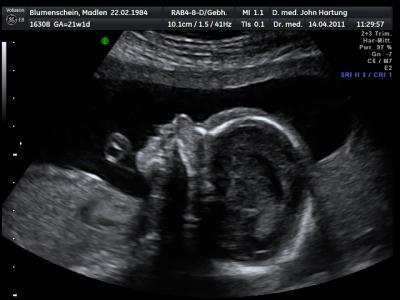

2. Foto

Bild zu